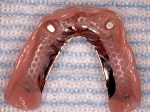

義歯の裏側